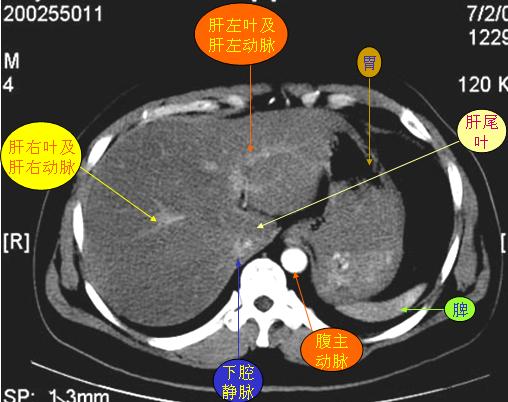

腹部ct解剖与基本病变